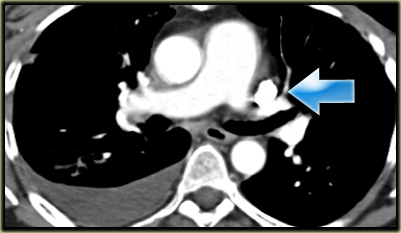

Describe the images on the left and then continue reading.

On the left side there is a vascular structure, that runs inferiorly below the level of the left hilum and enters into a dilated coronary sinus.

The diagnosis is left or double superior vena cava.